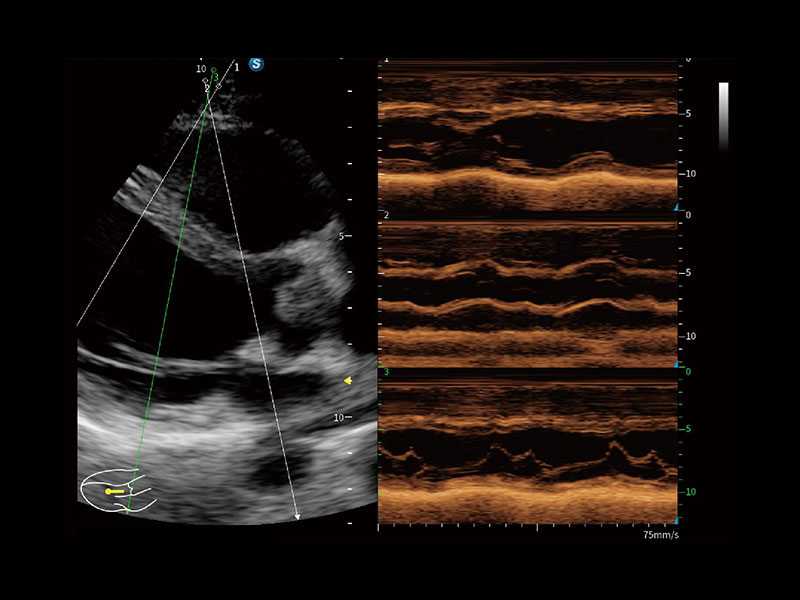

便携式彩色多普勒超声诊断系统

作为开立医疗全新打造的高端全域笔记本超声,X11集成了当前先进的硬件架构和精密的设计工艺,提升多科室临床医生在常规影像检查中的诊断能力,为临床提供全面的诊疗支持。